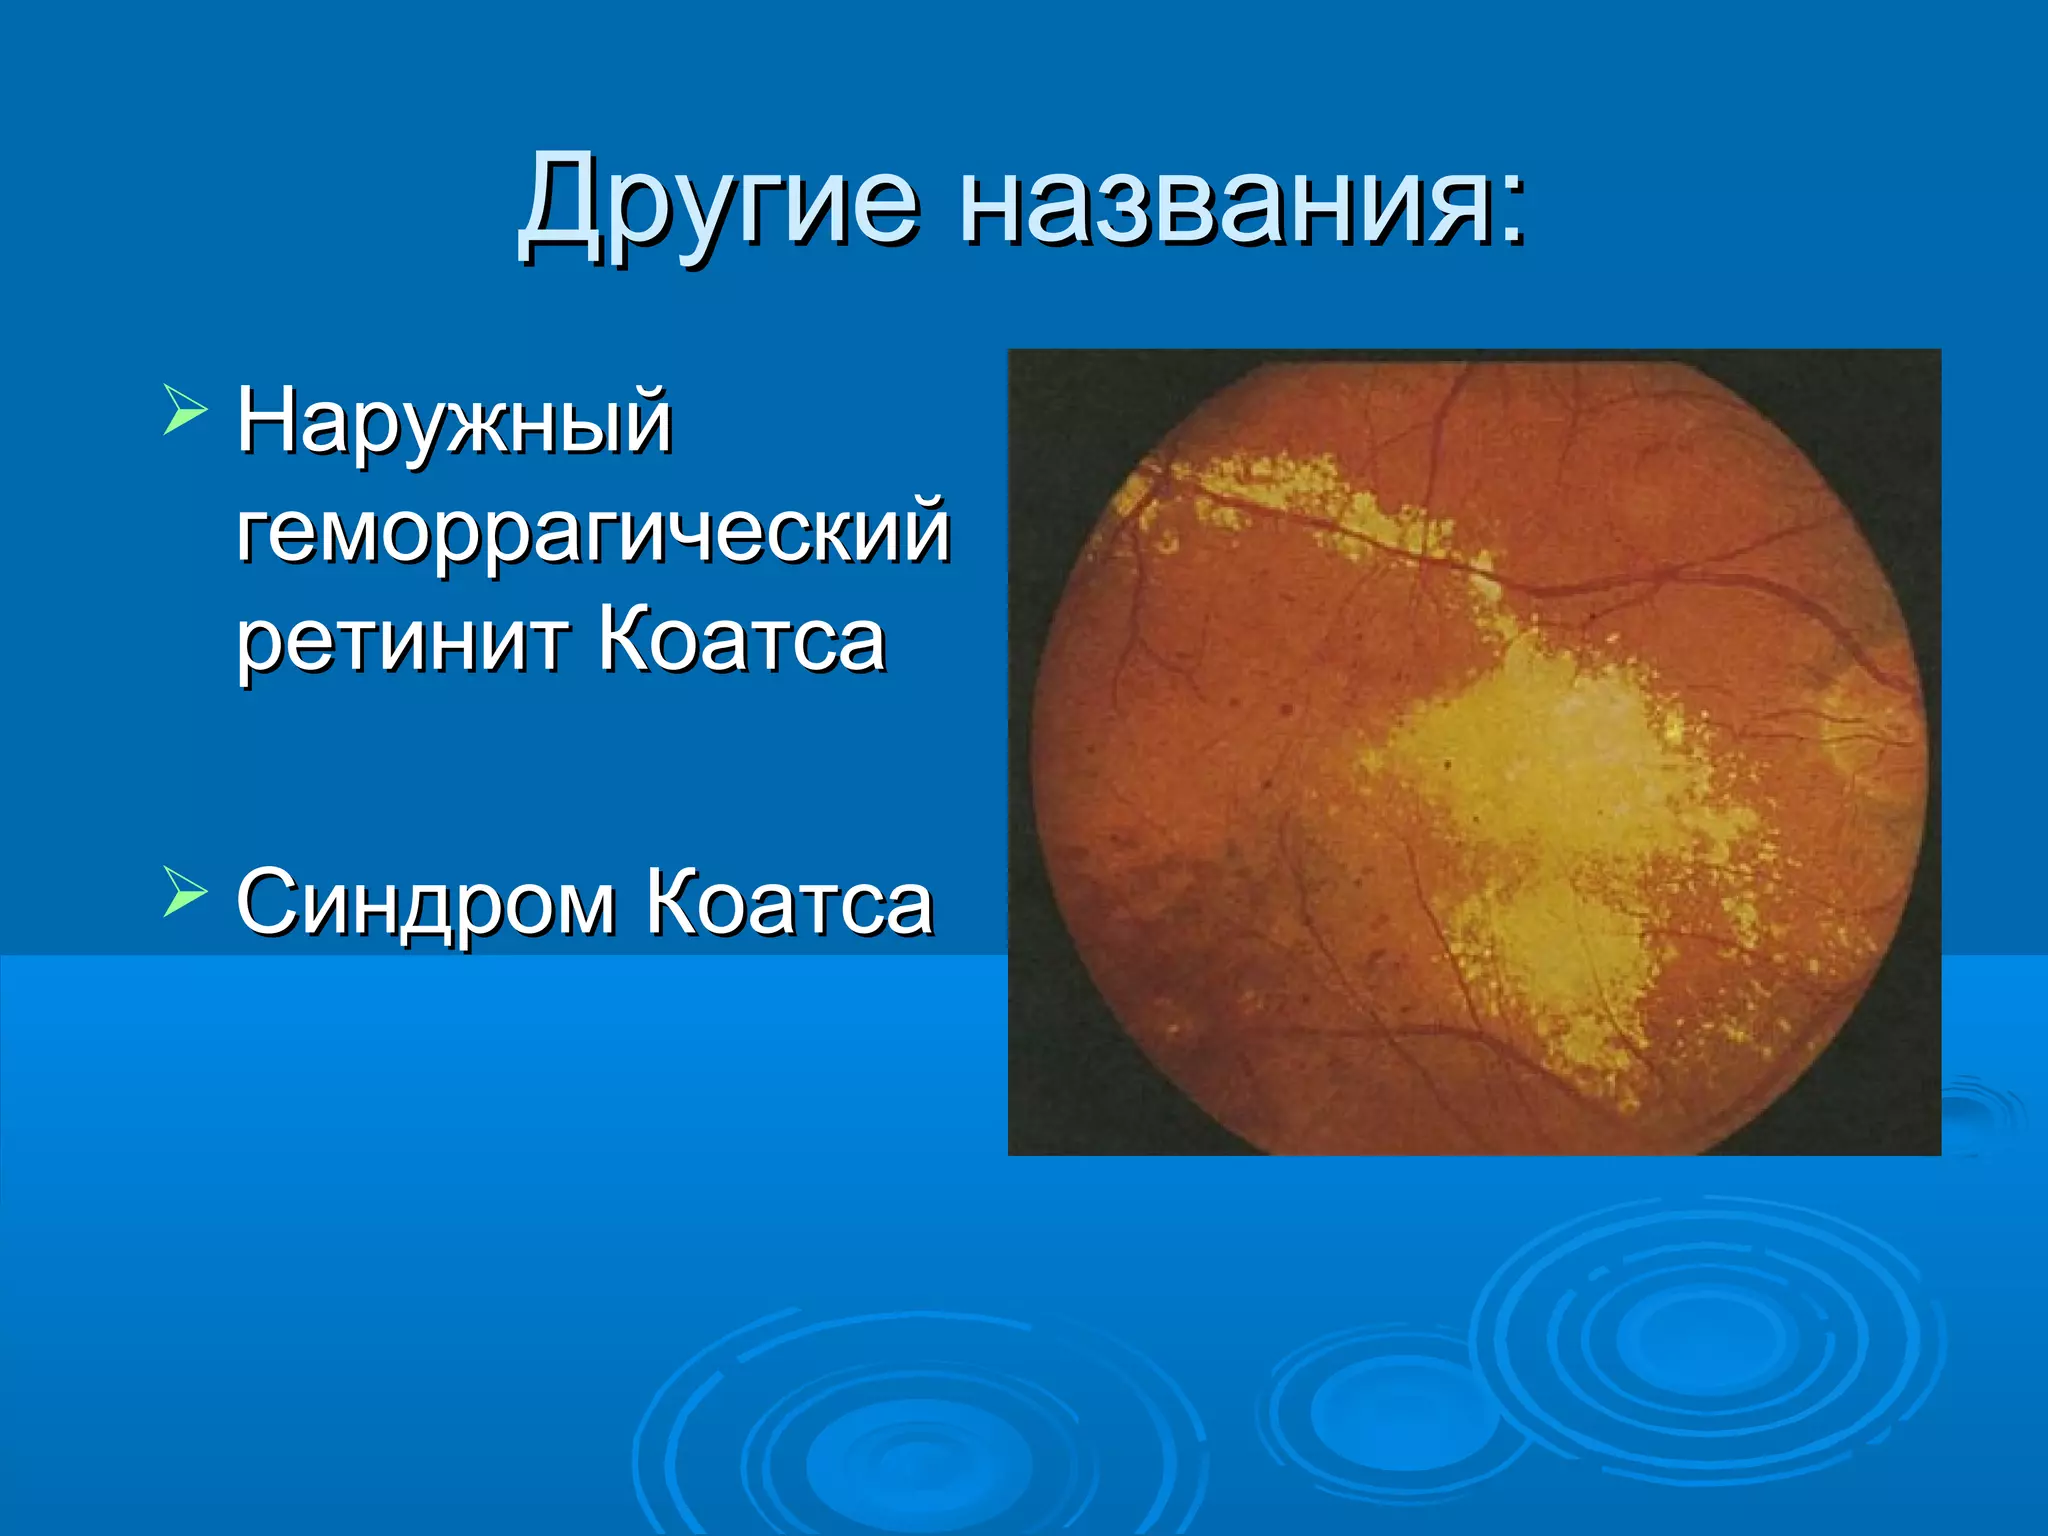

Болезнь Коатса - это идеопатическое заболевание, характеризующееся полиморфными изменениями сосудов сетчатки с массивной экссудацией, чаще всего у детей и подростков, с преобладанием среди мальчиков. Эпидемиология показывает, что заболевание проявляется, как правило, в возрасте 8-16 лет, но возможно его обнаружение и у взрослых. Основные проявления включают ретинальные аномалии, субретинальную экссудацию и постепенно прогрессирующую потерю зрения.